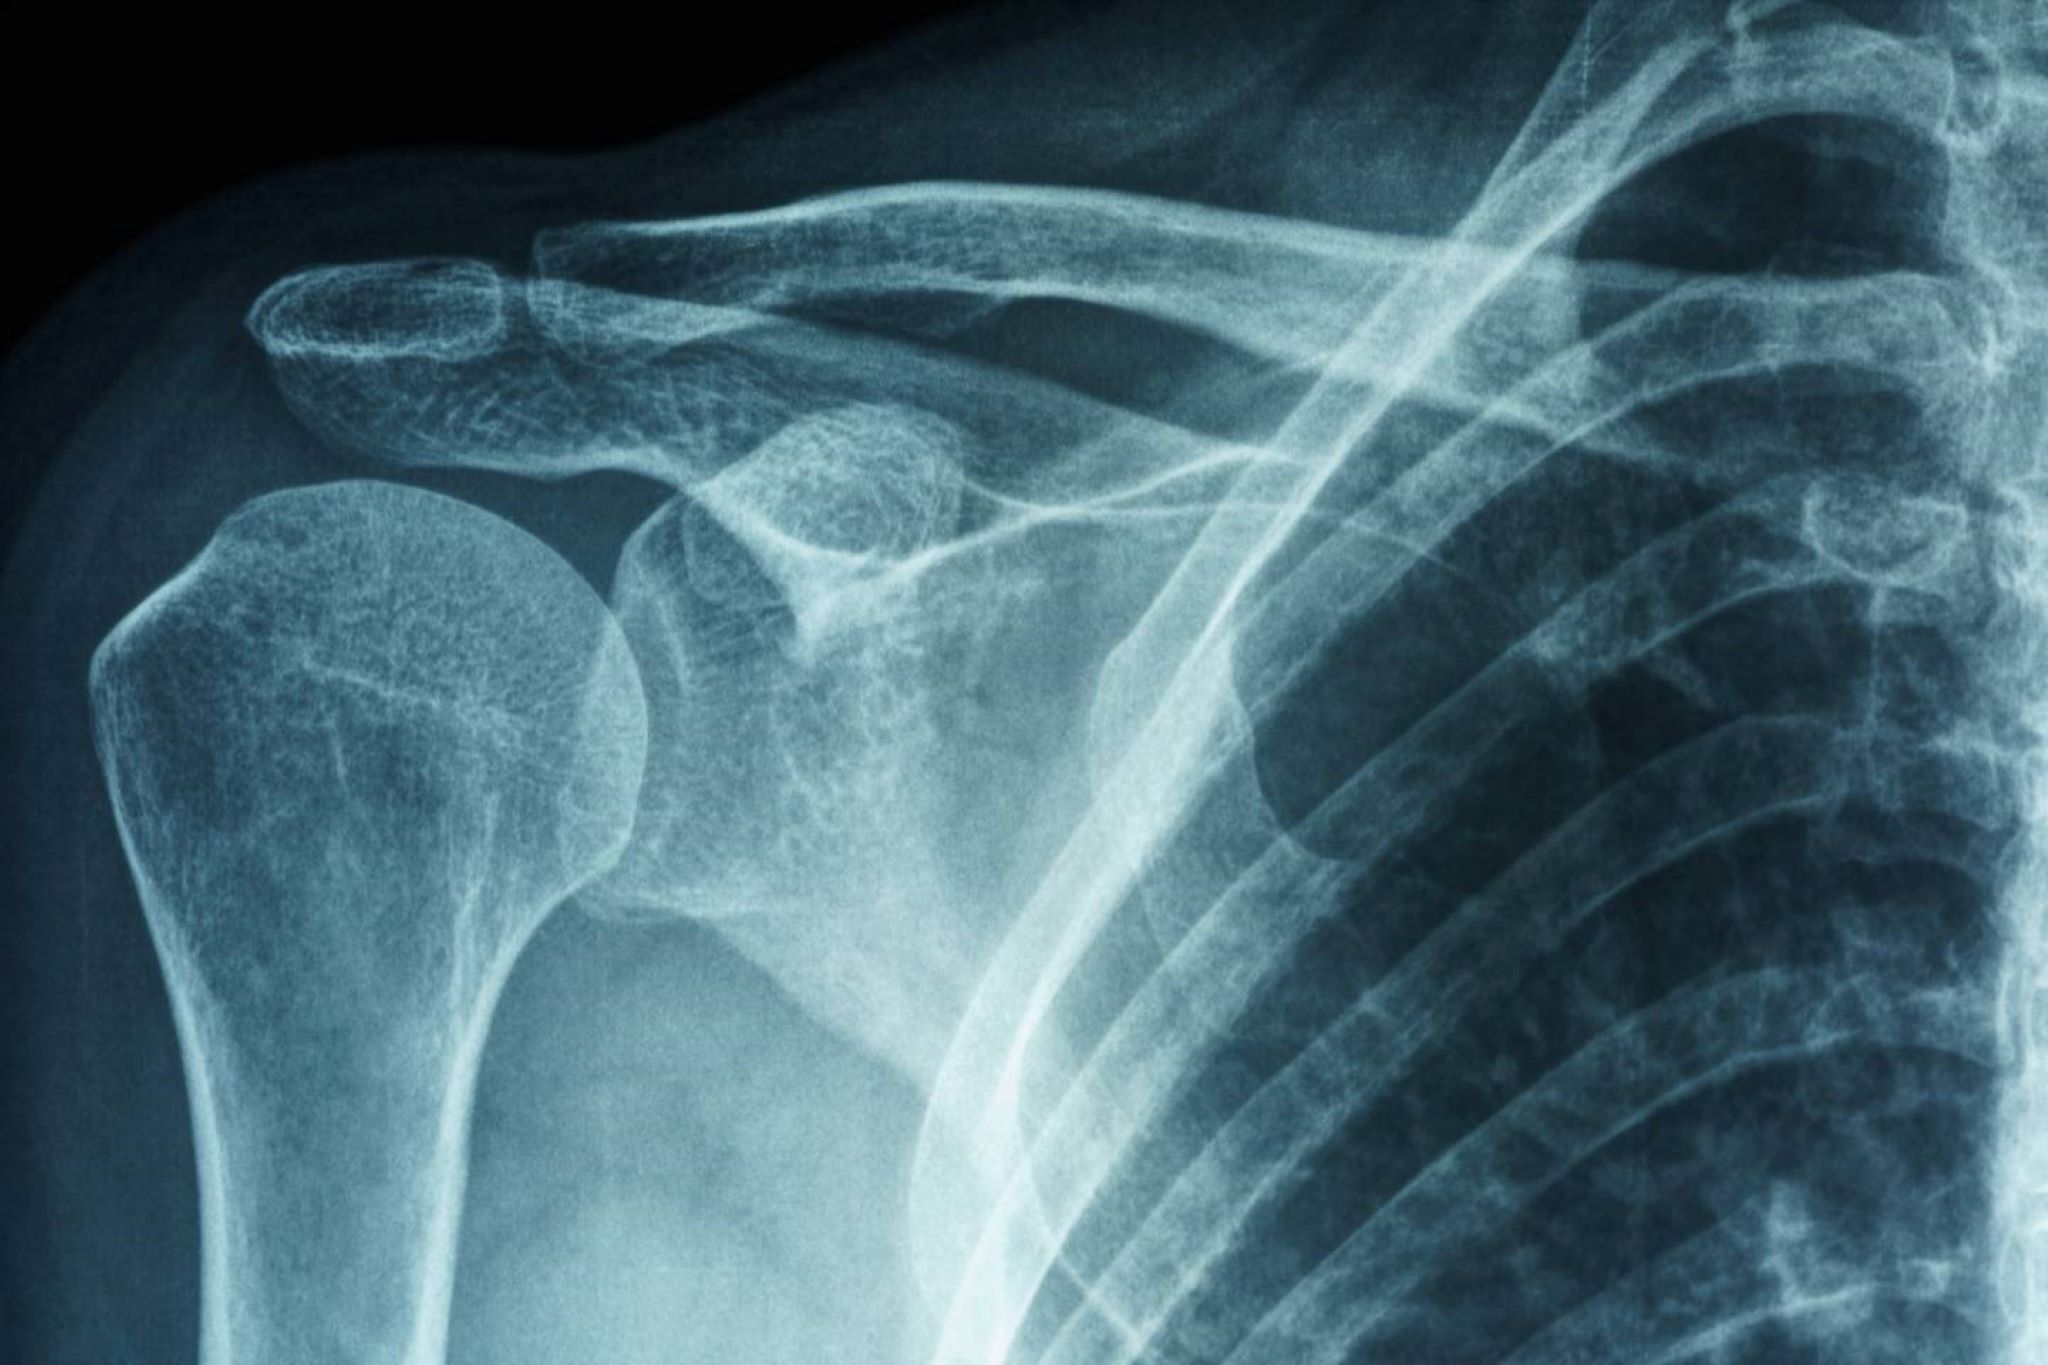

Παγωμένος ώμος

Ο παγωμένος ώμος (συγκολλητική καψουλίτιδα) είναι μια κατάσταση που προκαλεί δυσκαμψία και πόνο στην άρθρωση του ώμου. Τα σημεία και τα συμπτώματα περιλαμβάνουν έντονο πόνο, περιορισμένο εύρος κίνησης και δύσκαμπτη άρθρωση του ώμου. Τα συμπτώματα αρχίζουν σταδιακά και επιδεινώνονται με την πάροδο του χρόνου. Συνήθως επιλύεται μέσα σε ένα έως τρία χρόνια.

Τι διαχωρίζει αυτές τις δύο διαγνώσεις; Και οι δύο εμφανίζονται σαν επώδυνος, δύσκαμπτος ώμος. Όμως η κολλητική καψουλίτιδα (όπως υποδηλώνει το όνομά της) επηρεάζει τους ινώδεις συνδέσμους που περιβάλλουν τον ώμο και σχηματίζουν αυτό που ονομάζεται κάψουλα. Η κατάσταση που αναφέρεται ως παγωμένος ώμος συνήθως δεν περιλαμβάνει την κάψουλα.

Ακτινοσκοπικό φιλμ πρωτοπαθούς παγωμένου ώμου ή αυτοκόλλητης καψουλίτιδας Ασιατικής γυναίκας.